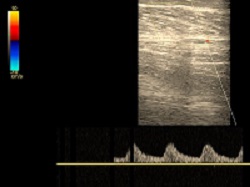

Żyły kończyn dolnych lub górnych

Wykrywa choroby układu żylnego: zakrzepicę, niewydolność zastawek żylnych, etiologię obrzęków, zmiany pozapalne i pozakrzepowe. Badanie żył głębokich i powierzchownych. Jednej lub obu kończyn.

Prawidłowa żyła podkolanowa.